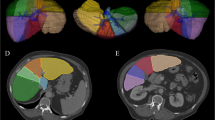

In this paper we present a set of 3D-rigid motion invariant texture features. We experimentally establish that when they are combined with mean attenuation intensity differences the new augmented features are capable of discriminating normal from abnormal liver tissue in arterial phase contrast enhanced X-ray CT–scans with high sensitivity and specificity. To extract these features CT-scans are processed in their native dimensionality. We experimentally observe that the 3D-rotational invariance of the proposed features improves the clustering of the feature vectors extracted from normal liver tissue samples.